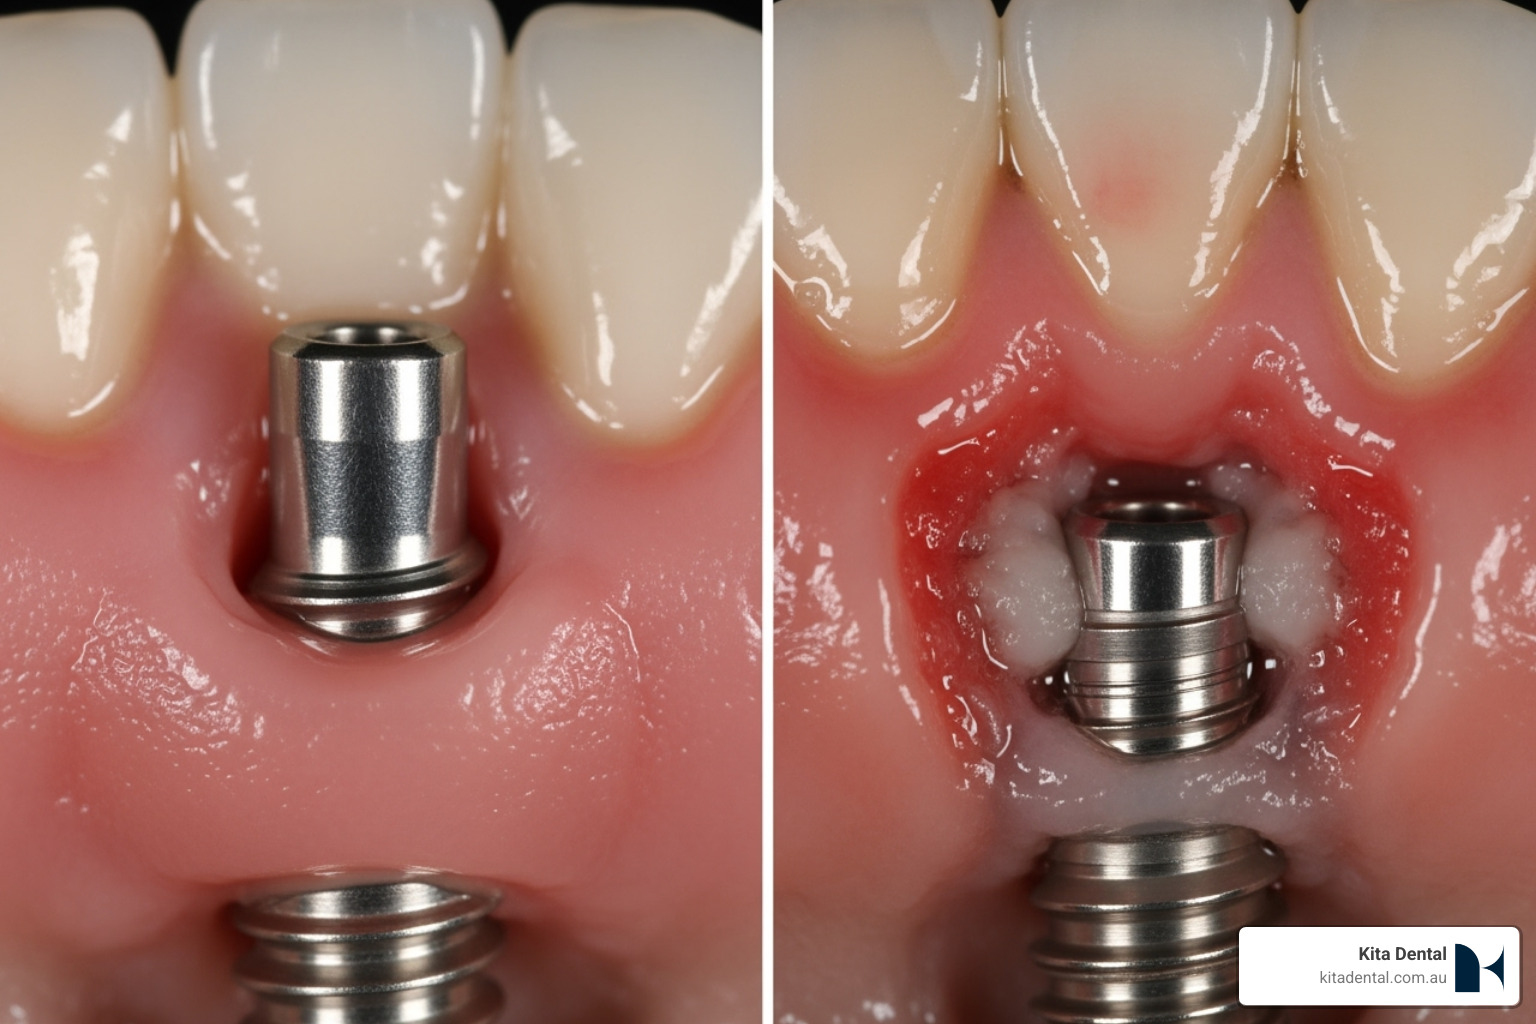

While implants can’t develop cavities, they’re vulnerable to peri-implantitis – a serious condition affecting 10-20% of implant patients when proper hygiene isn’t maintained. The good news? With the right cleaning routine, full arch implants boast a success rate over 95%.

The key difference lies in understanding that bacteria can still accumulate around your implants and prosthesis. Without proper cleaning, plaque buildup can lead to gum inflammation, bone loss, and potentially implant failure. Your gum health remains crucial for long-term success.

Understanding and Preventing Peri-Implantitis

Let’s talk about the condition that keeps implant patients awake at night: peri-implantitis. This inflammatory condition affects the tissues around your implant and can lead to bone loss and potentially implant failure. The good news? It’s highly preventable with proper care.

Recognizing the warning signs is crucial. Red, swollen, or tender gums around your implant are early indicators. Bleeding when brushing or flossing isn’t normal with implants. Pus discharge, persistent bad breath, or a feeling that your prosthesis is loose are all red flags that need immediate attention.

The most concerning sign is receding gums around the implant, which can indicate bone loss underneath. If you notice any of these symptoms, don’t wait for your next scheduled appointment – give us a call right away.

When Should the Prosthesis Be Removed?

Here’s a question we hear often: “Do you need to remove my full arch bridge for cleaning?” The answer might surprise you. Routine removal is not recommended and isn’t necessary for proper maintenance.

Current best practices, including guidelines from professional organizations, actually discourage routine removal unless specific problems arise. This is a shift from older practices where some dentists would remove prostheses every few months.

Removal becomes necessary when we can’t maintain proper hygiene with the prosthesis in place. Sometimes the design of the bridge creates areas where food and plaque accumulate despite your best cleaning efforts and our professional tools.

We might also consider removal if there are clear signs of peri-implantitis – things like pus, significant inflammation, or X-ray evidence of bone loss around your implants. Mechanical issues like a loose, damaged, or fractured bridge would also warrant removal.

Occasionally, we encounter stubborn calculus buildup that simply can’t be safely removed with the prosthesis attached. In these cases, temporary removal gives us the access we need for thorough cleaning.

The removal decision is always made by your dentist, as it involves carefully unscrewing the bridge from your implants. This process carries a small risk of screw complications and often requires replacing the prosthetic screws. Our goal at Kita Dental is always to maintain your full arch implants with the least invasive methods possible, keeping your beautiful smile intact and functional.